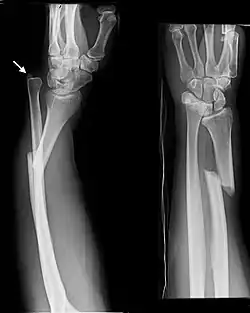

Fractures of the ulna can occur at different levels of the bone: near the wrist, in the middle or near the elbow.[2] The fracture may be confined to the ulna or accompanied with damage to the radius or the wrist or elbow joints.[2]

- Distal ulna fractures typically occur along with distal radius fractures.[3]

Monteggia Fracture (fracture of proximal ulna) -

Galeazzi facture (displaced fracture of the radius)